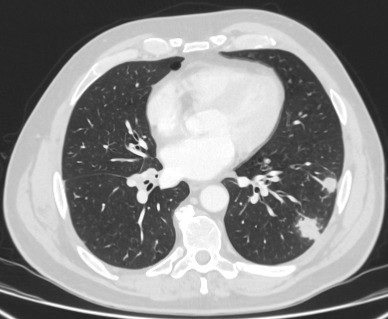

As causas restantes são infrequentes e incluem impactação mucoide, êmbolos sépticos, malformações arteriovenosas e amiloidose pulmonar.

[Figure caption and citation for the preceding image starts]: Tomografia computadorizada (TC) mostrando dois nódulos periféricos no lobo inferior esquerdo (um ligeiramente espiculado e outro com margens mais lisas) em paciente com febre, marcadores séricos inflamatórios elevados e hemoculturas confirmando Streptococcus intermedius. Ambos os nódulos foram completamente resolvidos após um ciclo de linezolida, condizente com êmbolos sépticosDo acervo de Dr. George Tsaknis, MD, PhD, FRCP (Londres), MRQA, MAcadMEd, PGCert; usado com permissão [Citation ends].